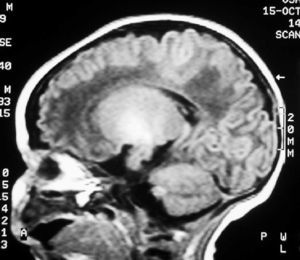

Fig. 2. Resonancia magnética. Secuencia T1 en plano sagital. Hiperintensidad de señal que de forma simétrica afecta a núcleos palidales y subtalámicos.

A las 48 horas de su ingreso presenta una crisis de hipertonía, motivo por el que se realiza una resonancia magnética.